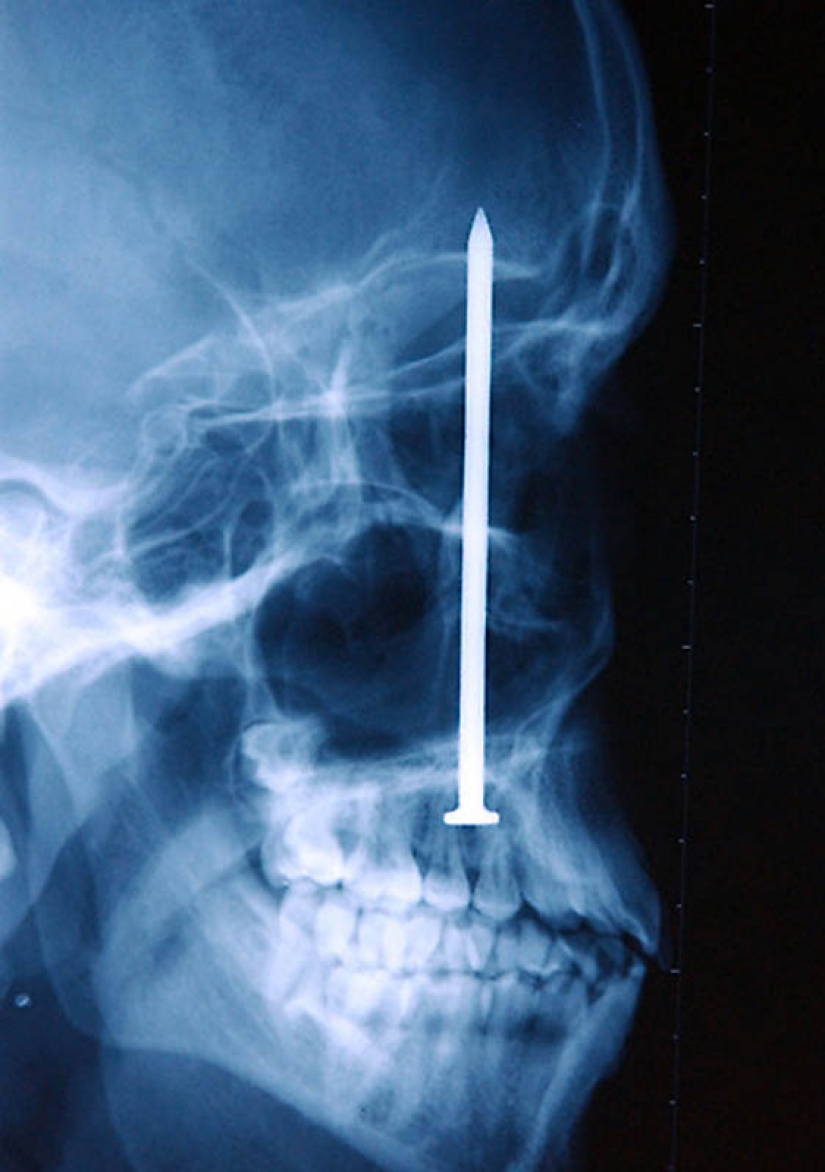

13. El clavo en el cráneo humano – el paciente se disparó accidentalmente a sí mismo con un martillo neumático. Él ni siquiera sabía que se pegó un tiro con una de 10 metros de la uña se encuentra sólo después de 6 días.